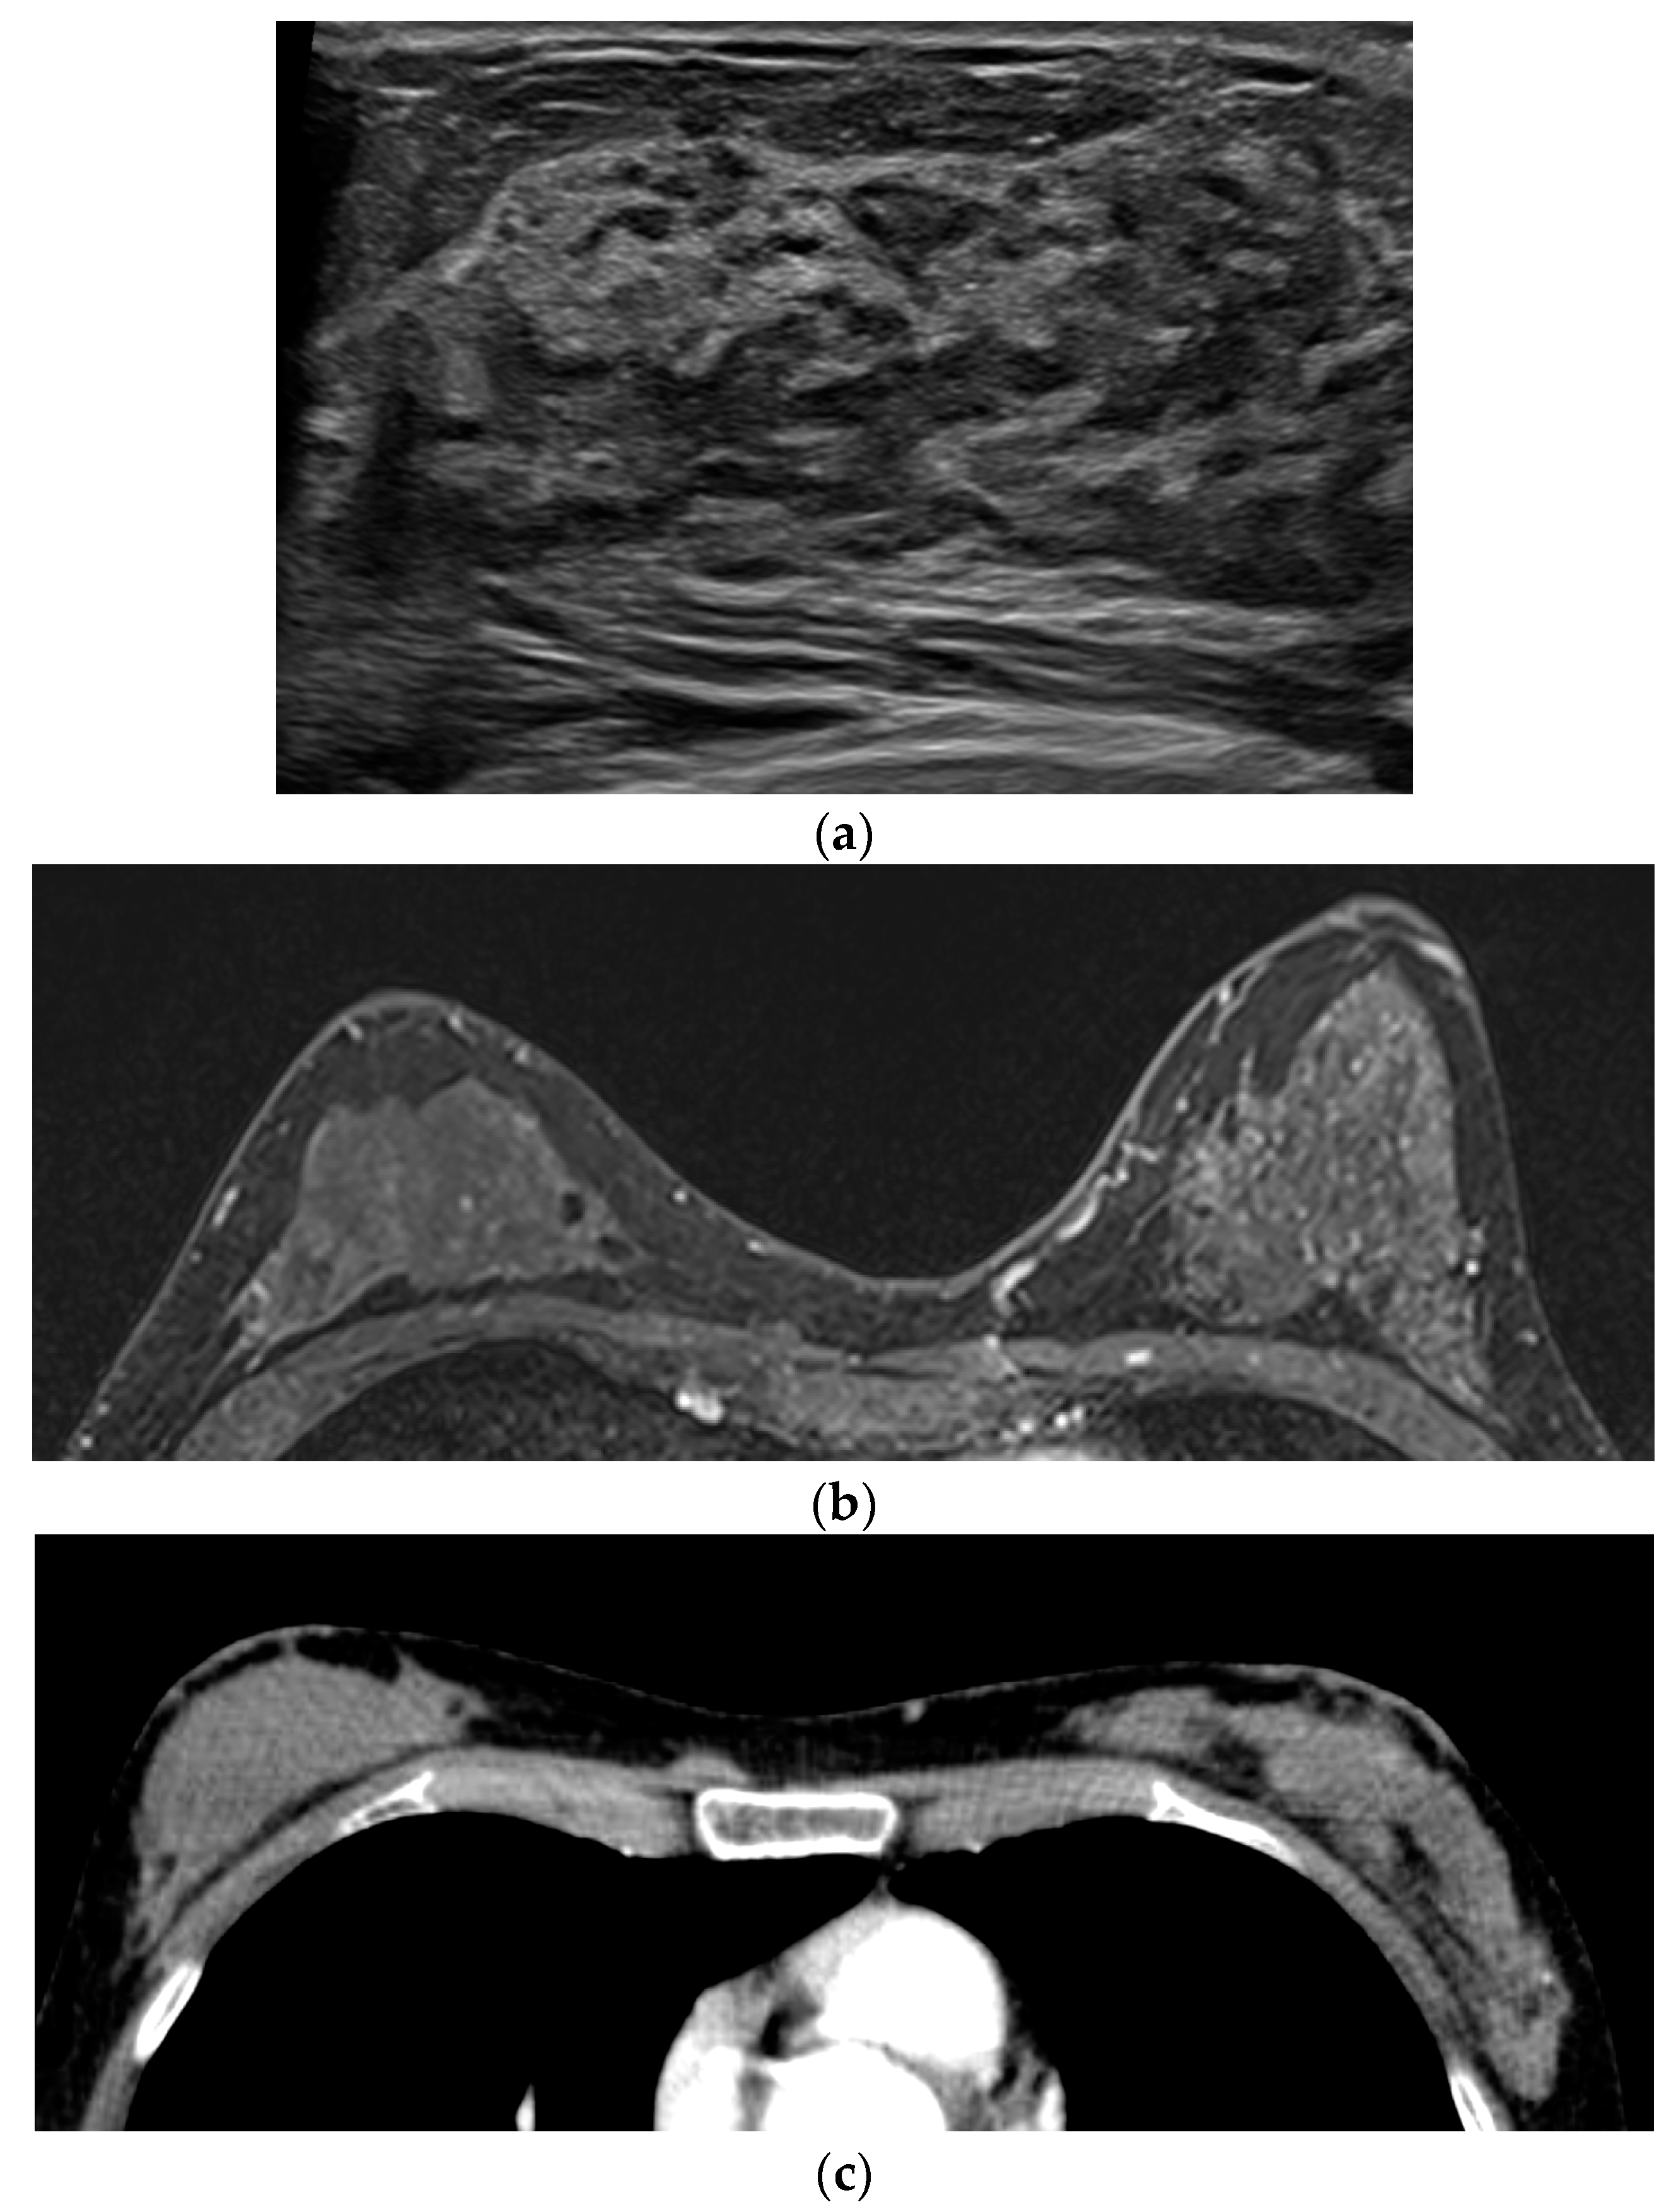

| 3 | 46 | mucinous carcinoma | 24 | Lt 2-o’ clock | moderate | Histologic feature | High | - | - | Mass |

| 4 | 57 | mucinous carcinoma | 9 | Lt 11-o’ clock periphery | mild | Histologic feature | High | - | - | Mass |

| 5 | 69 | mucinous carcinoma | 13 | Lt 9-o’ clock | moderate | Histologic feature | High | - | Mass | Mass |